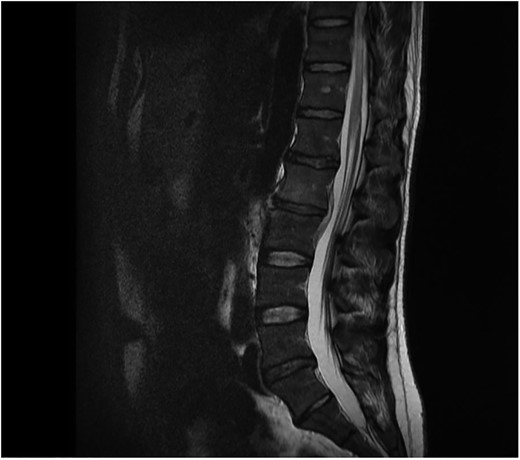

Neurosurgical advice recommended that due to the lack of neurological symptoms the patient could be treated conservatively with antibiotics. Microbiology advice was to treat the patient with IV flucloxacillin and oral rifampicin for at least 2 weeks and then to continue with oral antibiotics for at least a further 6 weeks depending on clinical improvement. Repeat bloods and MRI scans were performed to monitor the response to antibiotics (Fig. 2).

Sagital T1 MRI lumbosacral spine. 2 months later the epidural abscess has resolved and minimal marrow oedema is seen in L2 and L3 vertebra.

The patient completed a 2-week course of IV antibiotics followed by a further 12-week oral course. The patient responded well to antibiotic therapy as evidenced by normal inflammatory markers and resolution of osteomyelitis and epidural abscess on MRI.